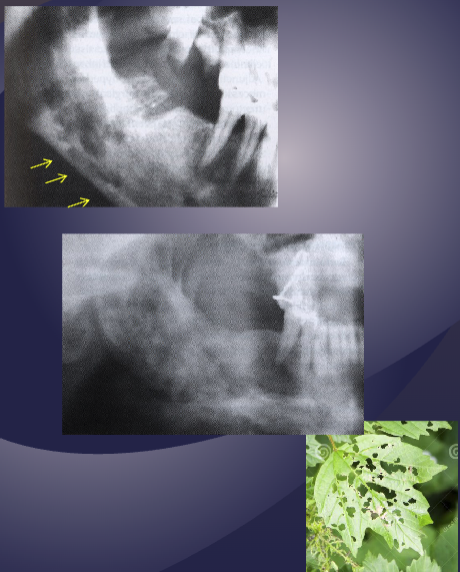

what is the black arrow pointing to

large sequestra caused by acute osteomyelitis

what are the arrows pointing to

fistula due to acute osteomyelitis

what is the white arrow pointing to

periosteal reaction due to acute osteomyelitis

pathologic fracture of the L mandible due to acute osteomyelitis